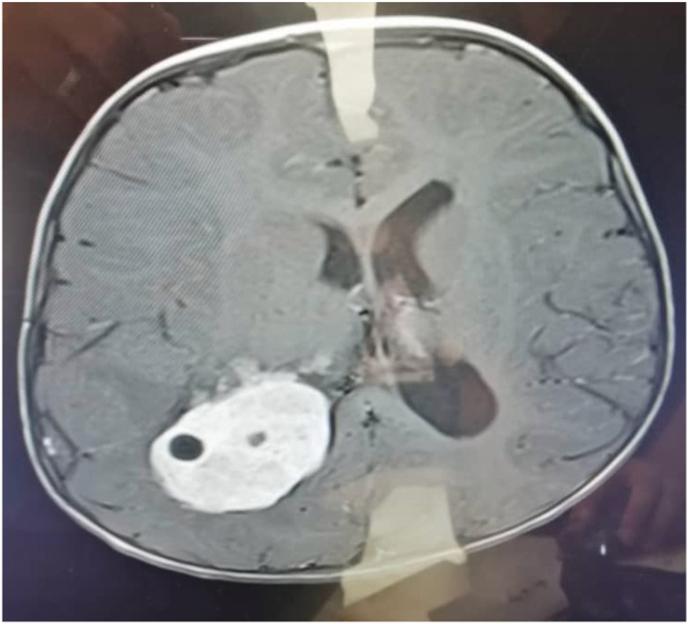

A two-year-old girl presented with a headache due to head trauma, normal consciousness, GCS 15/15, and without intracranial hypertension symptoms. Computed Tomography (CT) has shown a large heterogeneous lesion in the region of the right lateral ventricle. Magnetic resonance imaging (MRI) showed a large poorly-defined mass in the right lateral ventricle with mild dilatation of the ipsilateral lateral ventricle, and midline shift and marked edema surrounding it. In this case, the mass has been discovered by accident. The histological diagnosis was choroid plexus carcinoma (WHO grade 3), curettage of the right lateral ventricle was performed.